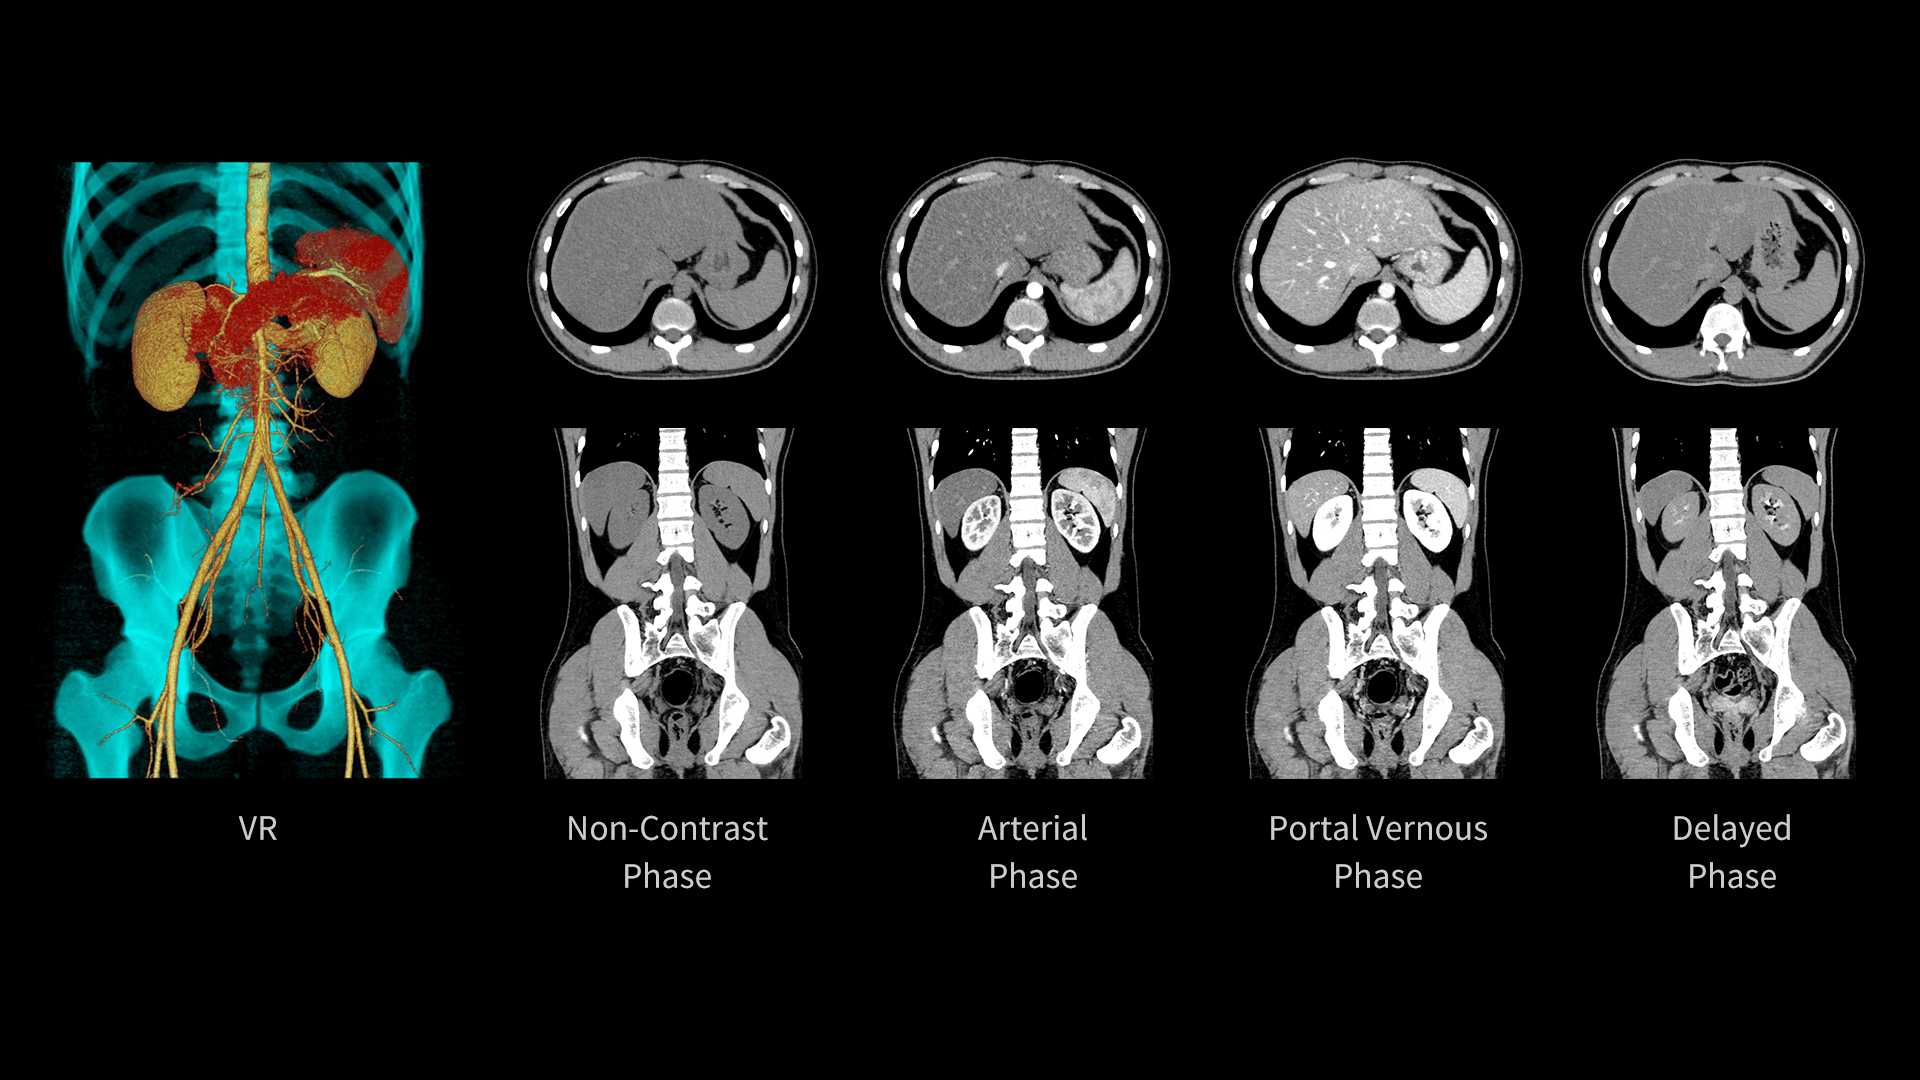

Imagistică Hepatică cu Contrast Multiphasic

uCT Orion Extra este echipat cu un detector Z de 40 de secțiuni, cu design inovator al chip-ului, care reduce nivelul de zgomot electronic. Această optimizare scade zgomotul în imaginile abdominale și îmbunătățește vizibilitatea limitelor leziunilor.

| Parametri scanare |

Timp rotație: 0.71 s / rotație kV: 100 mAs: 103 CTDIvol: 6.0 mGy Doză efectivă: 2.0 mSv |

| Parametri reconstrucție |

Matrice: 512 × 512 Grosime secțiune: 2.0 × 1.0 mm HIR: B_VSOFT_B WW/WL: 300/40 |

| Contrast |

350 mgI/ml 80 ml 2.5 ml/s |

Imagistică Multiphasică cu Substanță de Contrast

Tubul cu disipare ridicată de căldură (746 kHU/min) permite scanări continue și stabile, fără întreruperi cauzate de supraîncălzire. Astfel, uCT Orion Extra susține eficient examinările CT multiphasice cu contrast, oferind performanță constantă și imagini de înaltă calitate.

Timp rotație: 0.71 s / rotație kV: 100 mAs: 84 CTDIvol: 4.9 mGy Doză efectivă: 3.5 mSv Lungime scanare: 464 mm |